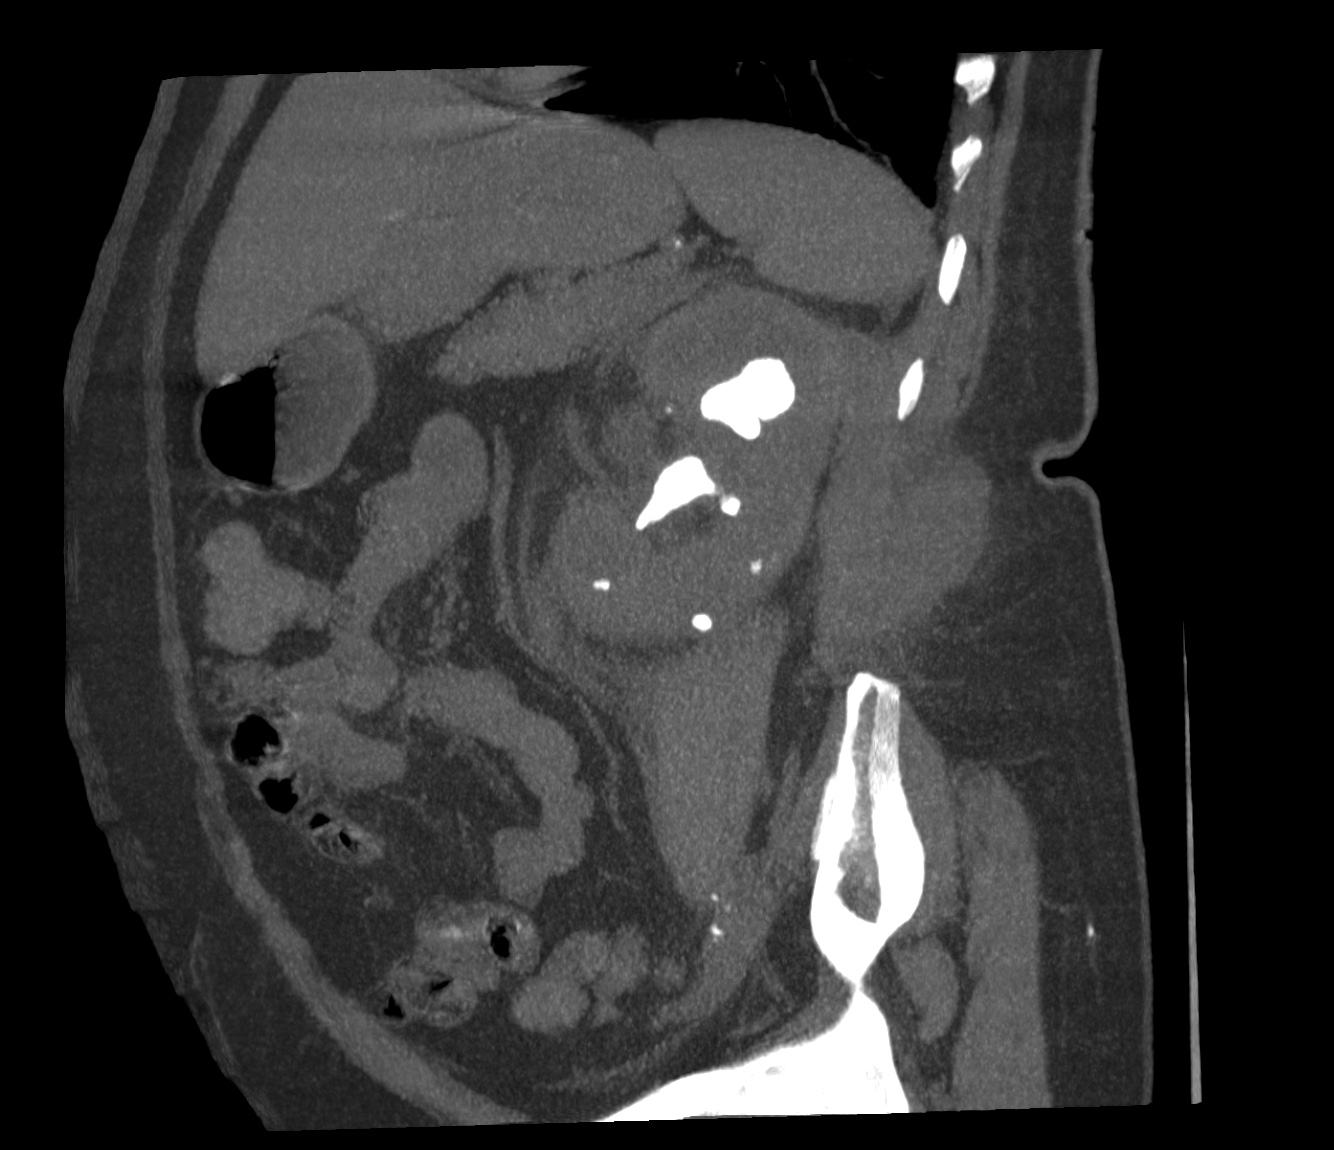

CASO 2: Paciente de 68 años con dolor en flanco izquierdo, fiebre y malestar general. A la exploración existe enrojecimiento de la piel con sensación de masa palpable y puño percusión muy positiva.

El paciente es alégrico al Iodo. Se realiza TC sin contraste para ampliar estudio.

Todos estos hallazgos están en relación con una Pielonefritis Xantunogranulomatosa que afecta al riñón derecho junto con una colección que ha fistulizado a región lumbar.

- Pielonefritis Xantunogranulomatosa.

- Es una forma infrecuente de pielonefritis crónica, de origen obstructivo, caracterizada por la formación de un absceso granulomatoso que puede extenderse al EPR-, severa destrucción renal y un cuadro clínico de fiebre, malestar general, dolor en el flanco y masa renal, a veces palpable.

- En placa simple podía verse un masa que renal con o sin borramiento de la línea del psoas. En ecografía, cálculos y aumento del tamaño renal en la forma difusa con múltiples áreas anecoicas correspondientes a las colecciones purulentas.

- Los hallazgos en TC pueden ser:

- Uni o bilateralidad de la lesión.

- Afección difusa o localizado.

- Litiasis de tipo coraliforme, calcificaciones intraparenquimatosas.

- Aumento difuso del tamaño renal.

- Áreas hipodensas o hipoecogénicas dentro de la lesión renal debidas a cálices dilatados, abscesos o áreas de necrosis parenquimatosa.

- Pobre o nula eliminación del medio de contraste en el riñón afectado.

- Compromiso inflamatorio que excede los límites del riñón y genera colecciones periféricas o extensión hacia vísceras vecinas.